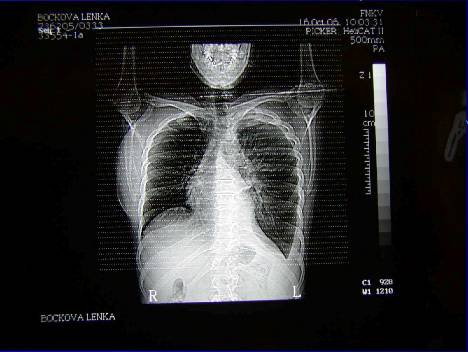

2.Duplicita (pac.H.M.– RTG,CT, CT-PET,UZ,bronchoskopie,cytologie, chirurgická intervence -biopsie -karcinoid)

Duplicita (pac.H.M. . ––RTG,CT,UZ, CT-PET,bronchoskopie,cytologie, chirurgická intervence-biopsie -karcinoid)